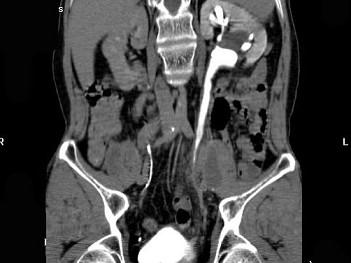

问题 男,59岁,反复尿频尿急尿痛4年余,尿常规检查:红细胞(+),白细胞(++),CT扫描如图示,下列说法正确的是 ( )

选项 A.左侧输尿管中下段输尿管管壁增厚,管腔狭窄 B.左侧侧输尿管上段扩张 C.考虑为输尿管结核 D.考虑为慢性输尿管炎 E.考虑为输尿管移行细胞癌

答案 ABD